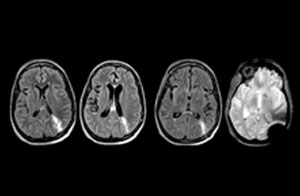

cervical spine mri in ed

Cervical spine routine exam

This patient presented with headache that was worse with neck flexion and we see a Chiari 1 malformation with low-lying cerebellar tonsils as well as some degenerative cervical thrombolytic change.